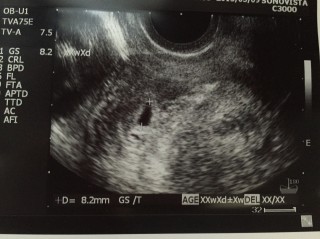

あまり早くても分からないと聞いていたので、この日まで頑張って待ちました。ちゃんと子宮の中に着床してますね、と先生に言われて一安心。8.2㎜でした。心拍確認まで待ち遠しいです!まだ小さいこの子だけど、お腹に負担をかけないように気をつけて過ごします!

結婚6年目で、待望の赤ちゃんです。 検査薬で陽性がでてから、今日の初診まで、 毎日ドキドキで、不安がありました。 不妊治療をしていたため、先生も笑顔で『順調ですよ』と言ってくれました!ちっちゃな赤ちゃんを確認した時は、幸せでいっぱいでした! 赤ちゃん、一緒にがんばろうね!